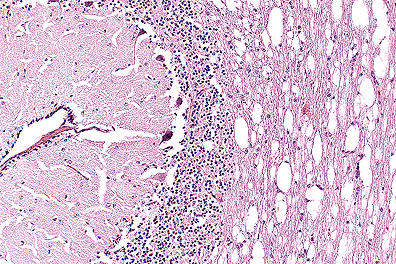

Numerous intracellular yeasts (H. capsulatum) within alveolar macrophages in a llama. (40X, PAS, 83K)

Histologically, sections of lungs contained numerous oval to irregularly shaped foci of caseous necrosis surrounded by marked infiltrates of macrophages and moderate numbers of neutrophils. Macrophages contained large numbers of 2 to 4 æm, round to oval, intracytoplasmic structures containing a single, usually eccentric, nucleus. Airways adjacent to the lesions contained moderate numbers of neutrophils and macrophages, many of which contained similar organisms. These organisms stained black with Gomori's methenamine silver stain, pink with periodic acid-Schiff (PAS) and did not stain with Giemsa stain. Narrow based buds were seen in special stains. No identifiable organisms were present in sections of liver.

Ultrastructurally, intracellular and extracellular organisms (1.0-1.9 x 1.6-4.0 æm) had small eccentric nuclei with mitochondria, vacuoles, whorled membranes, and occasional lipid droplets. The organisms were surrounded by an electron translucent fibrillar wall and a dense fibrillar outermost layer. Several organisms had bud-like projections. They lacked evidence of a kinetoplast and non-emergent flagellum typical of the amastigote stage of Leishmania sp.

AFIP Diagnosis: Lung: Pneumonia, pyogranulomatous, necrotizing, multifocal, moderate, with intrahistiocytic yeast, llama (Lama glama), camelid, etiology consistent with Histoplasma capsulatum.

Conference Note: Histoplasma capsulatum is a dimorphic fungus that grows as a nonparasitic, mycelial form in the soil and a parasitic, budding yeast in animals with body temperatures between 30 and 37oC. The mycelial form produces spherical microconidia ranging in size from 2-4 m, and club shaped macroconidia which range from 8 to 14 m . In tissue, H. capsulatum is a 2-4 m spherical or oval yeast that reproduces by narrow-based budding. Histopathological processing often causes the cytoplasm of H. capsulatum to shrink from the cell wall, creating a clear halo.